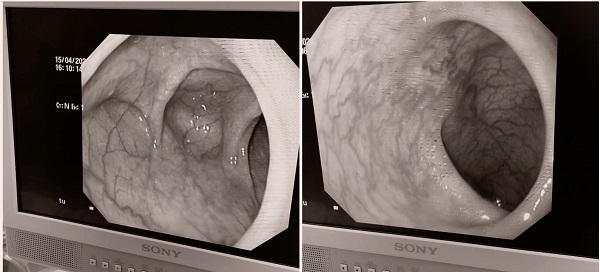

在开展工作的过程中,我遇到了一个很让人触动的病例。一个10岁伴有先天性红斑、脑萎缩的小女孩,自2019年出现无明显原因反复因黑便,贫血入院,每次予以输血和止血对症治疗,贫血纠正后出院。这样反复了八九次,最近的两次间隔仅仅半个月,血色素降至49g/L。我了解她的情况后,和小女孩的家长沟通进行相关检查以进一步明确病因,起初家长因经济条件一再拒绝,后来经过我耐心反复地解释、沟通,孩子家长终于同意做电子胃肠镜的检查。然后我与我院挂职该院担任副院长、脾胃病科副主任医师的康建媛医生沟通后,迅速联系了麻醉科,在该院开展了第一例无痛儿童胃肠镜检查。结合患儿临床表现及出血原因,为孩子下一步的诊疗及疾病的预后提供了明确的指导。